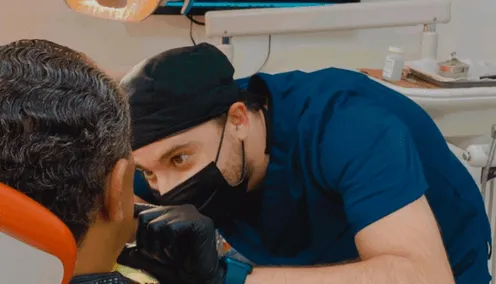

¿POR QUÉ ELEGIR AL DR. RICHARD PARA TUS IMPLANTES?

ESPECIALISTA EN CIRUGÍA ORAL E IMPLANTOLOGÍA

Contamos con profesionales con años de experiencia en implantes y además la tecnología para brindarte la mejor atención

ESTÁS EN BUENAS MANOS:

Dr. Richard González Plank

Cirujano Dentista

Especialistas en implantología Oral

y Reconstrucción.

Mejorando la salud bucal

de nuestros pacientes.